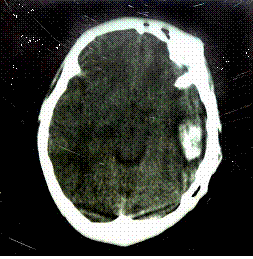

①腦震盪。以意識障礙及逆行性遺忘為特徵。輕者僅有短暫定向障礙,領會困難,分析與判斷力差,於數分鐘內恢復;重者可有意識喪失,多於半小時內恢復,醒後有逆行性遺忘、注意力渙散、思維困難、錯認或幻視,情緒障礙或行為異常,1~2周后逐漸消失。無明顯神經系統體徵。腦脊液檢查正常。②腦挫傷。傷後即有意識障礙,以朦朧、譫妄或混濁狀態常見,持續數小時至數日。有的經過一段清醒期後再次昏迷。醒後常有類似腦震盪的精神症狀。多有神經系統限局體徵、癲癇發作、顱內壓增高、腦膜刺激征或植物神經功能紊亂症狀。腦脊液呈血性,並可檢出各型吞噬細胞。腦電圖可出現瀰漫性高波幅慢波。③氣壓性腦損傷。多於傷後立即昏迷,持續數小時,醒後頭痛劇烈,記憶困難與遺忘,焦躁不安與情感淡漠。有時對聲音極其敏感或失聽與

顱腦損傷伴發精神障礙3.輔助檢查見顱腦損傷。